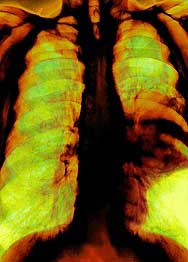

Have certain differences between cancer and other normal mesothelioma cancer. Since mesothelioma can find covering almost all major organs such as the heart, lungs and cancer of the body can be. Secondly, it is difficult to diagnose this type of cancer. Employees complain about physical pain, but family members work related fatigue, ignore it and fatigue. It is in the final stages, that her cancer patients with the entry. You may already know this fact � this is a threshold, patients must undergo treatment during the procedure.meso-info.net

Once this period is gone, the patient�s cancer may not respond to your treatment. Allegedly, fine powder, inhaled asbestos, will lead to cancer mesothelioma. The importance of this layer can never be underestimated. The protective layer is known and protect its regular lubrication authority from the influence and suddenly. This form of treatment of cancer, but only a small percentage popularization of treatment by the reaction of success.